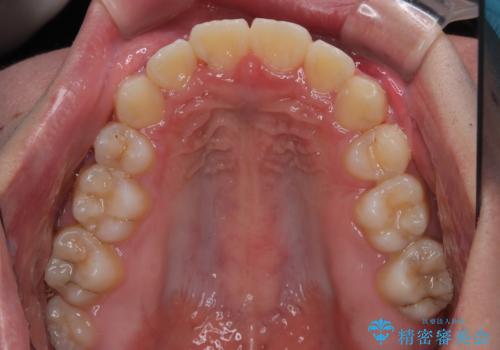

- 前歯のデコボコと口元の突出感を気にして来院された患者様です。

上下前歯がくちばしのように突出していたため、上下左右の第一小臼歯4本を抜歯し、ワイヤー装置にて矯正治療を行うこととしました。

上顎骨に対して下顎骨がやや前方位に位置しているため、下顎前歯をあまり内側に移動させることができず、口元の突出感改善は期待以上にはならないと予測しておりましたが、満足いくの引っ込み具合となりました。